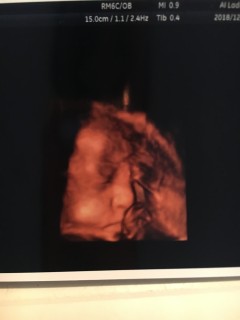

妊娠36週5日 36w5d の超音波 エコー 写真